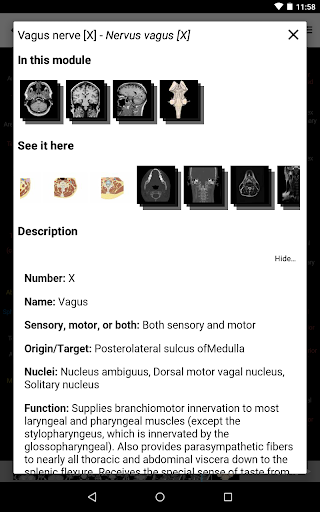

-In the details view of an anatomical structure related terms are now displayed